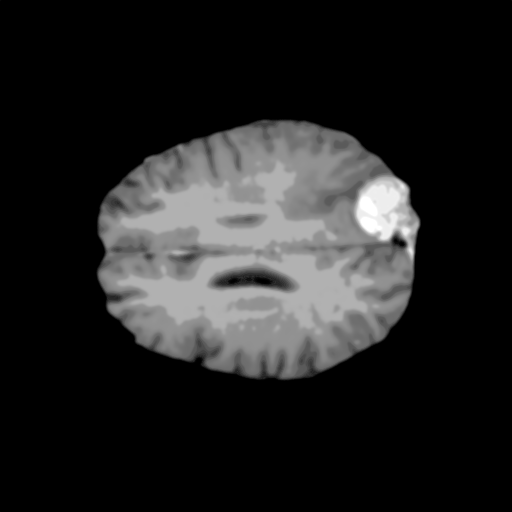

Extensive experiments have been performed in the current setup, and experimental outcomes are reported with the demonstration of numerical and statistical analyses using the proposed QFS-Net, QIS-Net [39], convolutional U-Net [18] and Residual U-Net (URes-Net) architectures [20]. The human expert segmented skull-tripped contrast enhanced DSC brain MR input image slices of size and ROIs are provided in Figure 5 as samples. The demonstration of QFS-Net segmented images followed by the essential post-processed outcome on the slice no. for class level with four distinct activation schemes () are shown in Figure 6. It is evident from the experimental data provided in Table LABEL:tab1 that the proposed QFS-Net performs optimally for the -connected quantum fuzzy pixel information heterogeneity assisted activation () with and gray scale set in comparison with other thresholding schemes and gray scale sets under the four evaluation parameters () [44]. The segmented tumors obtained using the proposed self-supervised procedure under class transition levels with four different thresholding schemes , , and are demonstrated in Figures 7- 8 for the class boundary sets and [39], respectively. The segmented images using the remaining two class boundary sets ( and ) [39] are provided in the supplementary materials section. The segmented ROIs describing the whole tumor region after the masking procedure using QIS-Net, U-Net and URes-Net are also reported in Figure 9.